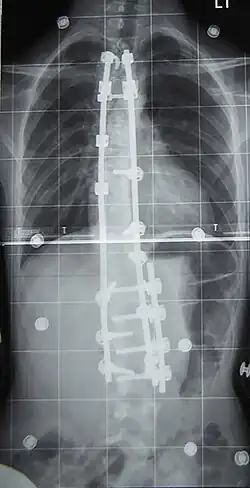

Radiographie post-opératoire d'une colonne vertébrale atteinte de scoliose.

Les traitements non chirurgicaux visent à limiter la progression naturelle des scolioses, notamment vers les formes graves, et à réduire le risque de complications respiratoires et douloureuses. Le traitement chirurgical peut, lui, tendre à la réduction de la courbure.

La prise en charge d'une scoliose fait appel à plusieurs spécialités médicales dans le but de limiter l’aggravation de la déformation de la colonne vertébrale. On emploie la kinésithérapie[41], le port du corset et la chirurgie en dernier recours. Cette dernière est réservée actuellement aux scolioses importantes.

Chirurgie

L'indication concerne environ 10 % des scolioses idiopathiques du sujet jeune[2] et concerne les scolioses importantes, avec un angle de Cobb dépassant les 50°. La technique consiste en la mise en place de deux longues tiges métalliques vissées dans les vertèbres, permettant le redressement de la colonne vertébrale, notamment avec la technique et le matériel de 3e génération proposés par Cotrel et Dubousset[45]. Les complications sont essentiellement locales mais il peut exister des étirements ou compressions de racines nerveuses dans moins d'un pour cent des interventions[46].

À l'issue de l'intervention (qui peut dans certains cas corriger totalement la scoliose), le rachis est bloqué de manière définitive. Les vertèbres libres de greffe devant travailler davantage pour « compenser » l'immobilisation du reste de la colonne, des douleurs dans le dos peuvent apparaître de façon imprévisible et à tout âge. Le rachis étant un flexible conçu pour bouger - et non être bloqué, on considère que l'opération ne règle pas entièrement le problème : on supprime un défaut (la courbure) pour en créer un nouveau : la rigidité du dos liée à l'opération